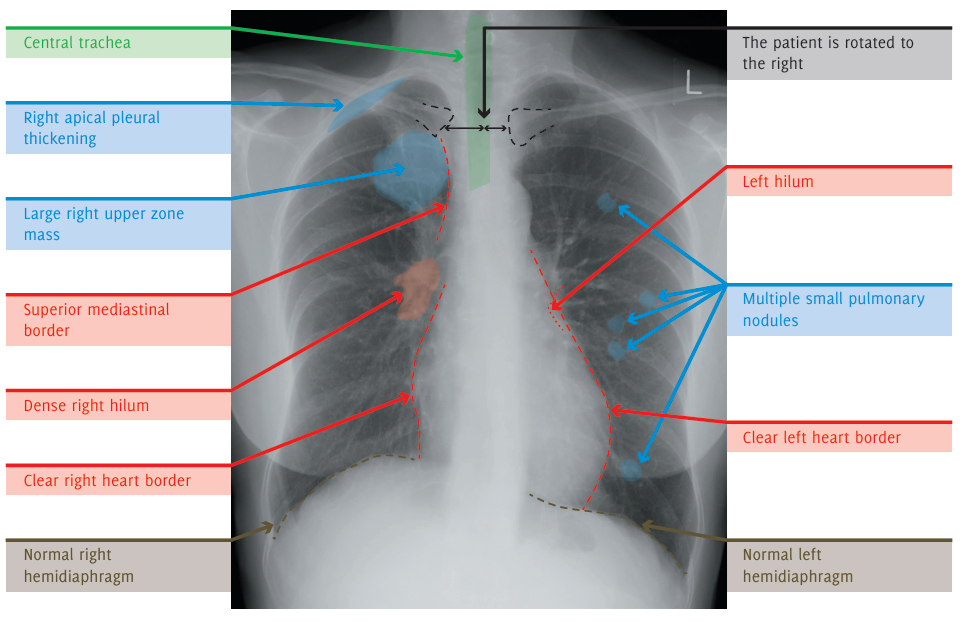

Una mujer de 60 años se presenta a su médico de cabecera con fatiga, pérdida de peso y sibilancias. No tiene antecedentes médicos significativos. No es fumadora. En el examen físico, presenta saturaciones del 99% en aire y no tiene fiebre. Se escucha sibilancia en el lóbulo superior derecho. Se solicita una radiografía de tórax para evaluar posible malignidad o EPOC.

La radiografía muestra una gran lesión redondeada en el lóbulo superior derecho del pulmón, asociada con múltiples nódulos más pequeños. Esto es altamente sospechoso de un cáncer pulmonar primario del lóbulo superior derecho con metástasis pulmonares. El hilio derecho denso es sospechoso de enfermedad nodal hilar. La relevancia del engrosamiento pleural apical derecho no está clara.

Las pruebas iniciales de laboratorio pueden incluir hemograma (FBC), análisis de electrolitos y función renal (U/Es), proteína C reactiva (CRP), pruebas de función hepática (LFTs) y perfil óseo.

El paciente debe ser referido a los servicios de neumología/oncología para un manejo adicional, que puede incluir biopsia y discusión en un equipo multidisciplinario (MDT). El tratamiento, que puede incluir cirugía, radioterapia, quimioterapia o tratamiento paliativo, dependerá del resultado de la discusión en el MDT, las investigaciones y los deseos del paciente.

Se debe realizar una tomografía computarizada (TC) de tórax y abdomen con contraste intravenoso para estadificación.